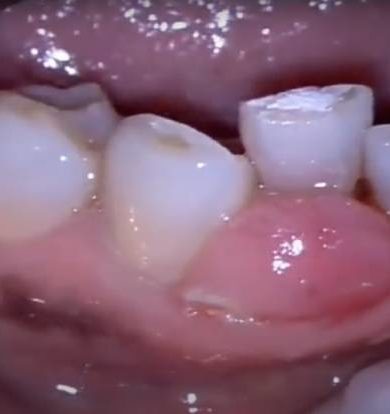

Moses Dental – Gingivectomy